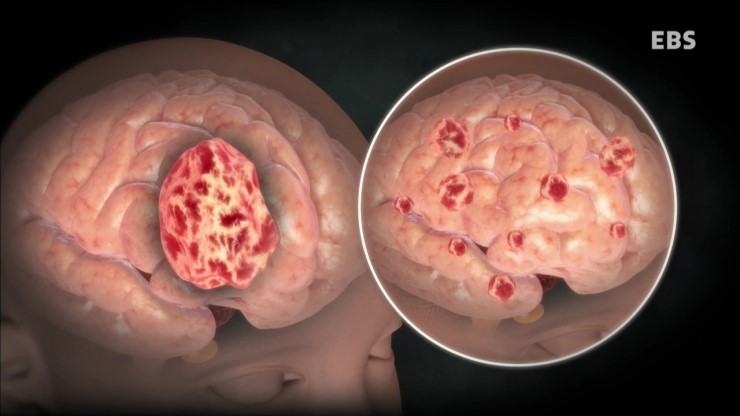

뇌종양은 뇌조직이나 뇌를 싸고 있는 막에서 발생된 종양과 머리뼈나 주변 구조물에서 멀리 떨어진 부위에서 뇌조직이나 뇌막으로 전이된 종양을 말합니다. 또, 뇌종양은 양성과 악성으로 나눌 수 있는데요. 양성 뇌종양은 성장속도가 느리고 주위 조직과의 경계가 뚜렷한 특성을 지니고 있습니다. 악성 뇌종양은 뇌암이라고도 말하며, 성장속도가 빠르고 주위 조직으로의 침투 능력이 강하여 주변의 정상 뇌조직을 빠른 속도로 파괴합니다.

뇌종양의 가장 흔한 증상은 두통입니다. 간질 발작이 나타나거나 점진적인 운동 및 감각 능력이 소실됩니다. 오심, 구토가 나타날 수 있으며 시력이 손실되거나 복시가 나타날 수 있습니다. 또한, 뇌종양의 크기와 위치에 따라 다양한 증상이 나타날 수 있습니다. 뇌종양을 의심하게 하는 증상들은 다음과 같습니다.

뇌종양 의심 증상

1) 성인에서 첫 간질발작

2) 팔다리의 점진적 운동 및 감각능력 소실

3) 불안감(특히 두통과 관련)

4) 한쪽 또는 양안의 시력손실

5) 소아에서의 오심, 구토

6) 복시(특히 두통과 관련)

7) 현기증을 동반하거나 그렇지 않은 청력손실

8) 말하기 능력의 점진적 손실